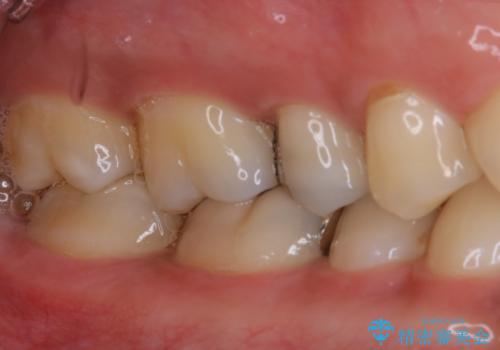

- 銀歯のやり替えをご希望された患者様です。手前の歯にもプラスチックと歯の間に虫歯が出来ていたため、両方とも適合の良いセラミックで補綴しました。

- セラミックインレー7.7万円・仮歯1.1万円・フルジルコニアクラウン7.7万円(税込)費用は治療当時の料金となります